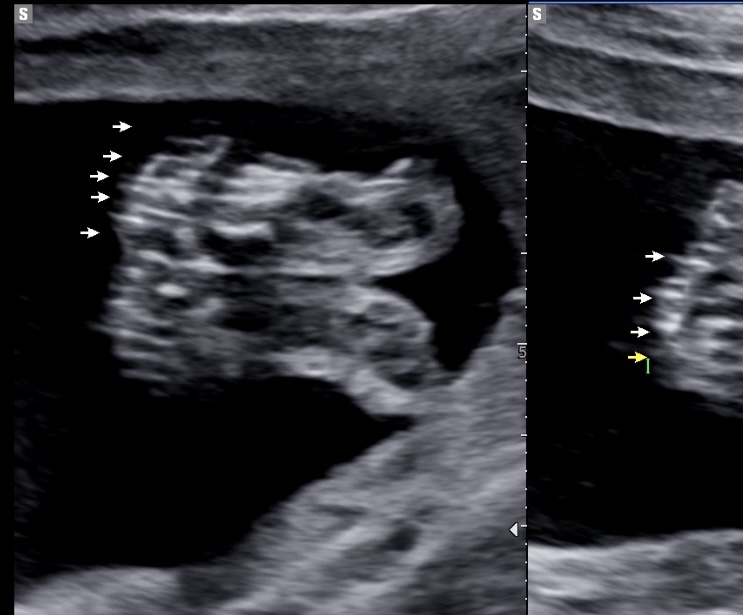

임신 21~28주 후기 : 온몸이 불편해지는 순간

21주의 시작! 기대하고 기대하던 정밀 초음파를 보러갔다. 아가 손발은 잘 있는지, 어디 아픈곳은 없는건지...